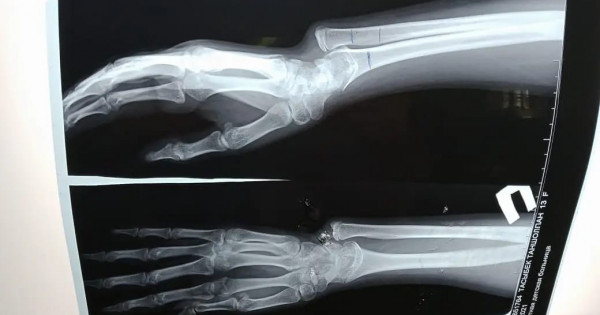

Naýqas osydan birneshe jyl buryn qolyn aýyr jaraqattap, shyntaq súıegi ósip, kári (lýchevaıa) súıegi óspeı qalǵan. Saldarynan qolyndaǵy súıekteri qısaıyp, ózdiginen qımyl jasaýǵa kedergi keltirgen.

«Ota jasalǵan naýqas úsh aı buryn qalalyq klınıkalyq balalar aýrýhanasyna keńes alýǵa kelgen bolatyn. Teksere kele naýqasta jaraqattyń saldarynan súıegi qısaıǵany anyqtaldy. Operasııany birden jasamadyq. Sebebi mundaı ota balanyń súıek ósýi toqtaýǵa jaqyndaǵan kezde jasalady. Operasııa kezinde qatty ósip ketken súıekti qysqartyp, óspeı qalǵan súıekke jalǵap, arnaıy qurylǵymen bekitip berdik. Mundaı otany birinshi ret jasadyq. Osyǵan deıin súıegi qısyq ósken naýqastarǵa ota jasaý úshin Nur-Sultan qalasyndaǵy emdeý mekemelerine joldama arqyly jiberetinbiz. Endi mine mundaı otany ózimiz jasaýǵa daıynbyz» deıdi ortoped-travmatolog Baǵjan Turdyqulov.